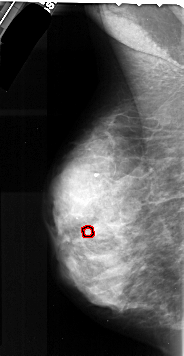

FILE: A_1043_1.LEFT_MLO.OVERLAY

TOTAL_ABNORMALITIES 1

ABNORMALITY 1

LESION_TYPE CALCIFICATION TYPE AMORPHOUS DISTRIBUTION CLUSTERED

ASSESSMENT 4

SUBTLETY 2

PATHOLOGY MALIGNANT

TOTAL_OUTLINES 1

LEFT_MLO LINES 5326 PIXELS_PER_LINE 2746 BITS_PER_PIXEL 16 RESOLUTION 42 OVERLAY